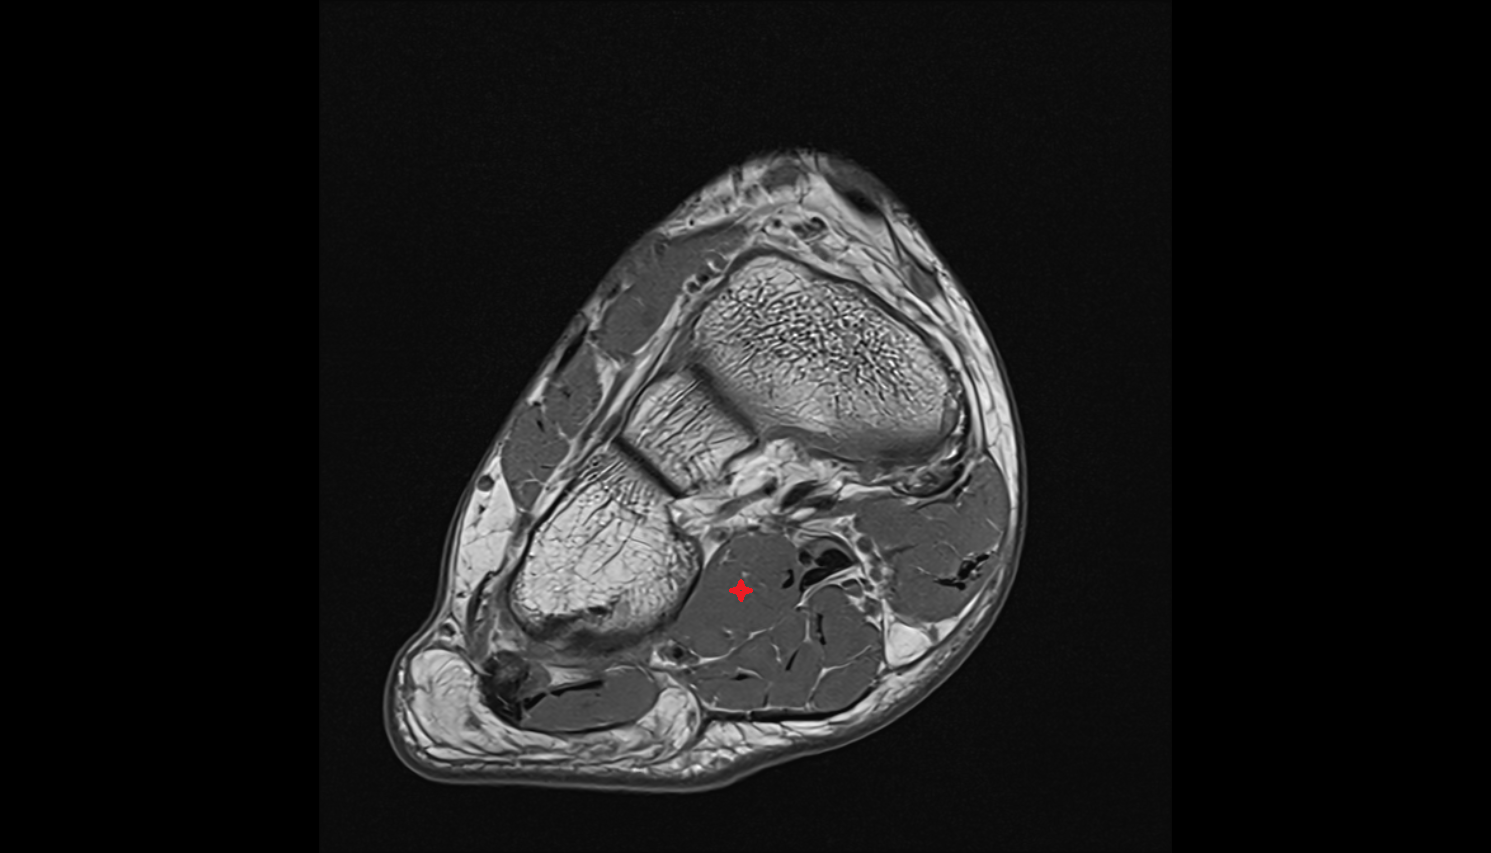

- Calcaneus

- Sustentaculum tali

- Tibialis posterior muscle

- Flexor digitorum longus muscle

- Flexor hallucis longus muscle

- Quadratus plantae muscle

- Abductor hallucis muscle

- Flexor digitorum brevis muscle

- Abductor digiti minimi muscle

- Flexor retinaculum

- Inferior calcaneal nerve (Baxter’s nerve)

- Medial plantar nerve

- Lateral plantar nerve

- Posterior tibial artery